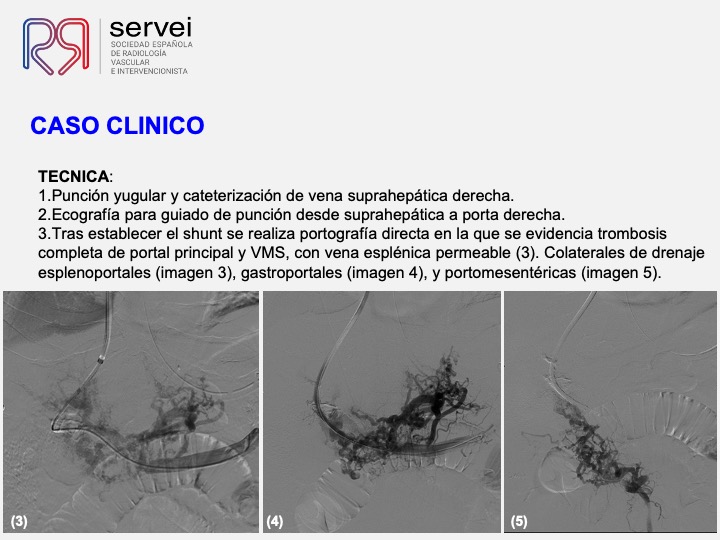

- Isquemia mesenterica venosa 06

- Isquemia mesenterica venosa 07